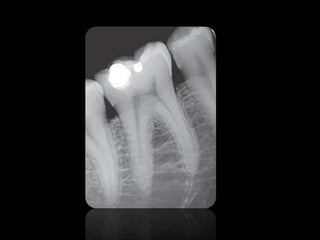

Interpretacion radiográfica

Clase de Interpretación Radiografica presentada por la Dra. Joyce Roca

3.

• Las imagenes

son llamadas radio opacas. • Las imagenes son llamadas radio lúcidas.

ABSCESO PERIAPICAL